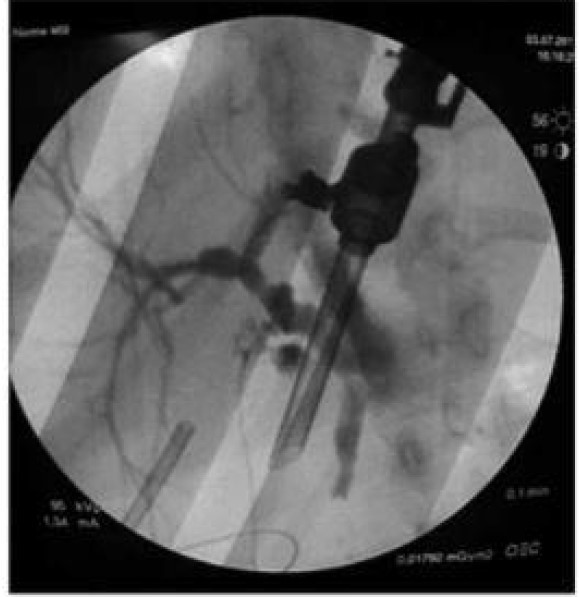

Qual o exame e o diagnóstico

Colangiografia intraoperatória (injeta no ducto cístico), mostrando coledocolitíase (interrupção do fluxo distal)